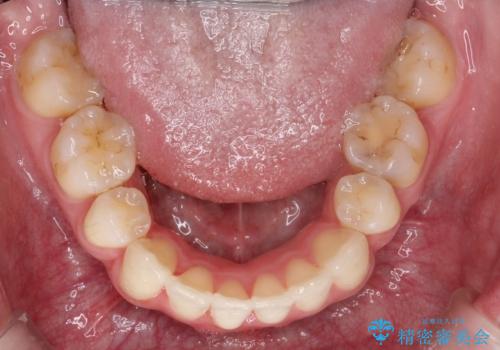

- 前歯が出ているため口が閉じにくく、横顔が気になるとのことで来院された患者様です。。

上下の前歯が前方に傾斜しており、口唇の突出感がありました。

上下左右の前から4番目の歯を抜歯して、上下の前歯を後方に移動させる計画としました。